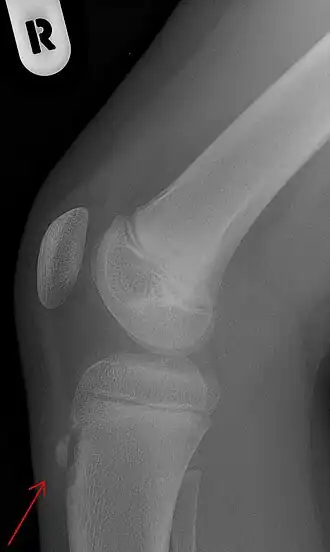

Zijdelingse röntgenfoto van een knie met de ziekte van Osgood-Schlatter | ||||

De ziekte van Osgood-Schlatter[4][2] is een ziekte waarbij er pijn optreedt op de plaats van de aanhechting van de kniepees aan het scheenbeen. Hierbij ontstaat er een zeer gevoelige bobbel op het scheenbeen net onder de knie. De ziekte is voor het eerst beschreven door de Amerikaanse chirurg Robert Osgood en de Zwitserse chirurg Carl Schlatter, onafhankelijk van elkaar in 1903.[5][6]